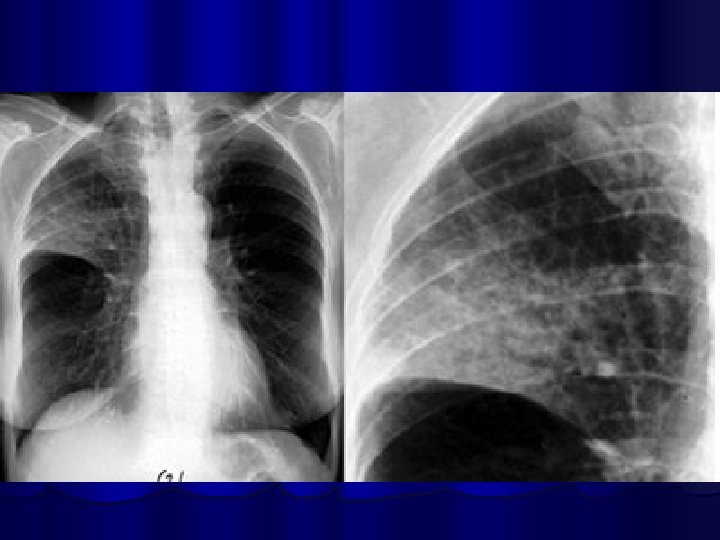

Bronchopneumonia/ Diffuse Pneumonia